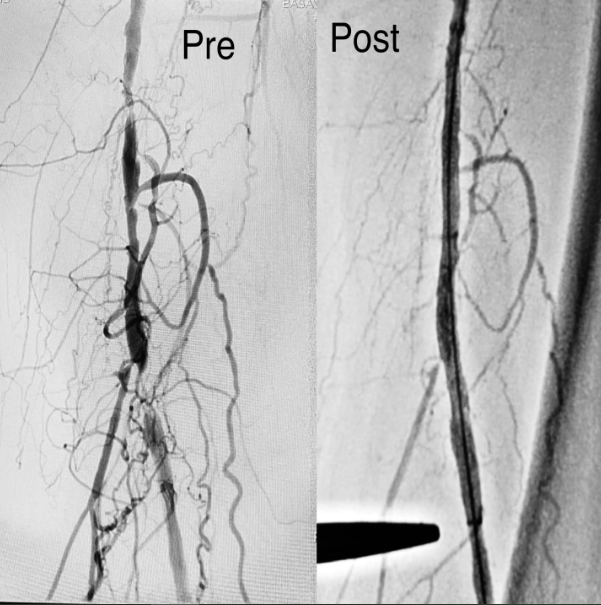

One of the most commonly performed procedures at Dr. Kumar Kenchappa's clinic is angioplasty, which involves opening up blocked or narrowed coronary arteries to restore proper blood flow. This procedure is crucial for patients who are at risk of heart attacks or suffering from coronary artery disease. Dr. Kenchappa's precision and skill in performing angioplasties make him one of the leading specialists in the city.